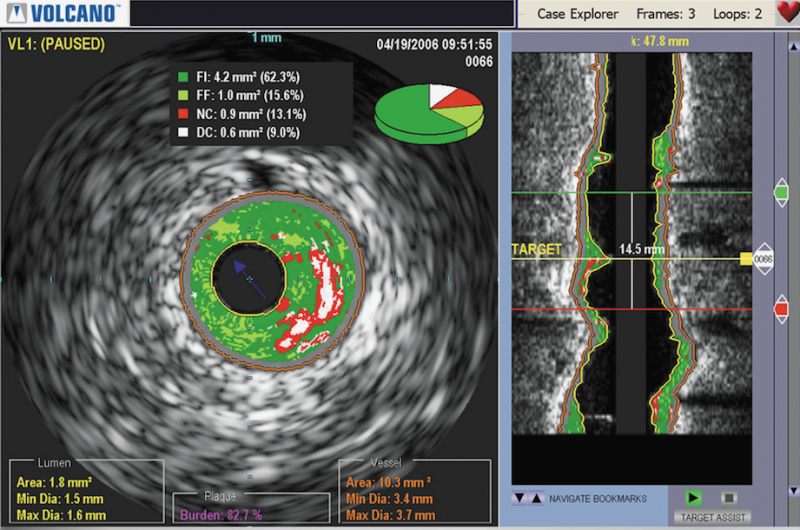

Shimadzu Medical Systems announced the first United States installation of its Trinias C-12 crossover system at First Coast Heart & Vascular Center in Jacksonville, Fla. This first North American installation of the Trinias angiographic system was completed by Shimadzu dealer/partner CMS Imaging of North Charleston, SC and began operation at the medical center in late January.